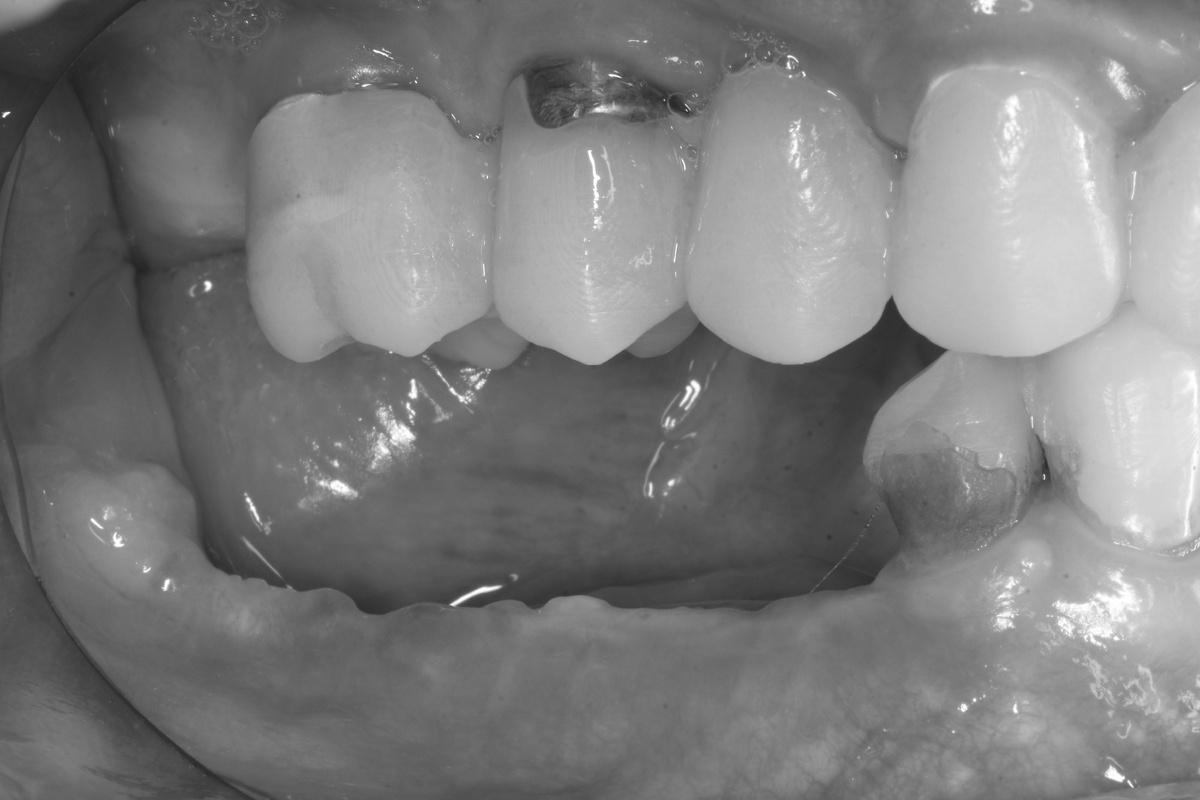

Как выглядит результат спустя несколько лет — на пяти фотографиях ниже

Верхний зубной ряд:

-

Справа. Протяженный мост на 5 единиц с опорой на 3 свои зуба

Передние зубы. Две одиночные коронки + мост на 3 единицы

Слева. 4 коронки с опорой на 4 импланта + зуб мудрости

Нижний зубной ряд:

Справа. Мост на 3 единицы с опорой на 2 импланта + дистопированный зуб мудрости

Передние зубы. 8 собственных +/- живых зубов

Слева. 1 свой зуб под коронкой, 2 коронки с опорой на 2 импланта + дистопированный зуб мудрости

Результат спустя 1 месяц — на трёх фото ниже

Обратите внимание на то, что осталось от нижней челюсти слева. Сказать, что кости не осталось совсем — ничего не сказать